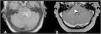

To describe the magnetic resonance imaging (MRI) findings for the most common inflammatory and immune-mediated diseases that involve the brainstem.

ConclusionInflammatory lesions involving the brainstem are associated with a wide range of autoimmune, infectious, and paraneoplastic syndromes, making the differential diagnosis complex. Being familiar with these entities, their clinical characteristics, and their manifestations on MRI, especially the number of lesions, their shape and extension, and their appearance in different sequences, is useful for orienting the radiological diagnosis.